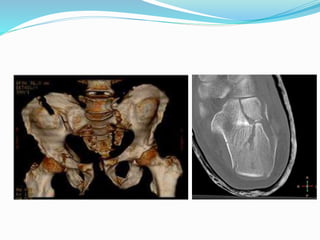

 Fractures/subluxation/dislocations requiring

transaxial/ 3D reconstruct like carpal/ tarsal/ tibial

plateau/calcaneal/pelvic